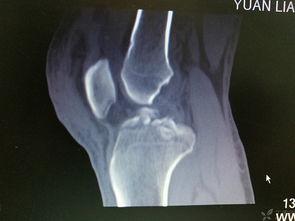

3. 骨折线

骨折线是骨头断裂的地方,这张照片清晰地展示了骨折线的位置。骨折线可能会呈现出直线、曲线,甚至波浪形。骨折线的长度和宽度也会因人而异。